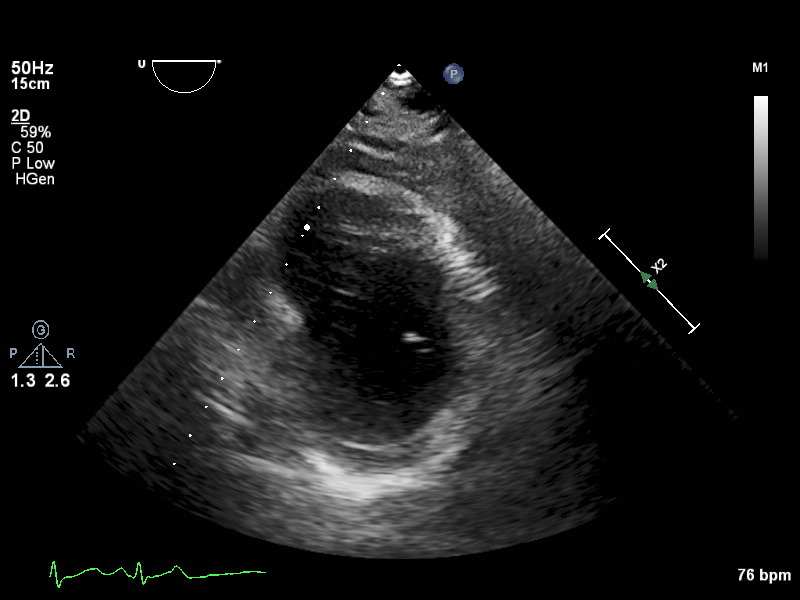

PSAX (7 views)

ImageView NameDescription

psax-lv-mid psax-lv-mid Left ventricle mid level

psax-lv-apex psax-lv-apex Left ventricle apex level